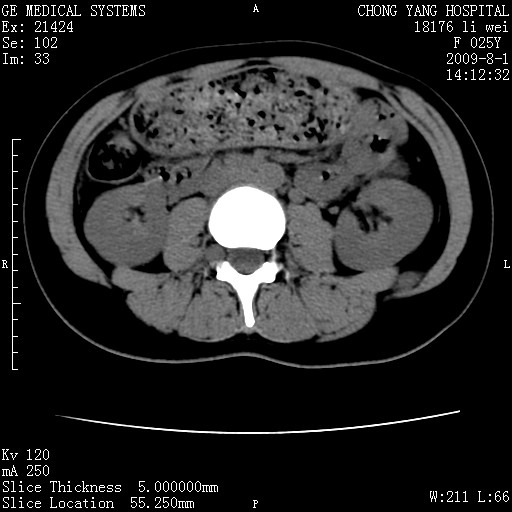

以下是引用pujunzhi在2009-8-1 20:23:00的发言:[br]胸椎旁及背部肌间良性病变,范围广,边界清,沿肌间生长,考虑淋巴管瘤、血管瘤,建议增强扫描。

以下是引用拾荒者在2009-12-30 21:45:00的发言:[br]ct21383:神经纤维瘤病( nf) [br] [br] 神经纤维瘤病。四肢都有,影响美观,四肢上的手术了。[br] [br] [br]谢谢!